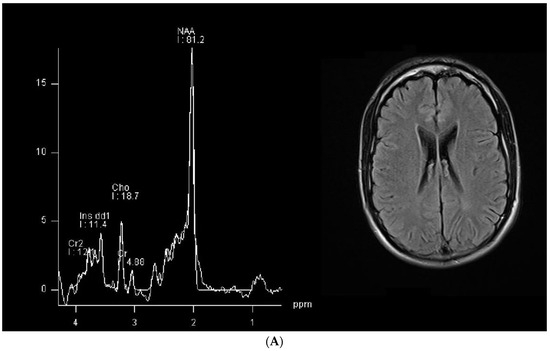

Selective Alteration of the Left Arcuate Fasciculus in Two Patients Affected by Creatine Transporter Deficiency

by Maurizio Balestrino, Enrico Adriano, Paolo Alessandro Alì and Matteo Pardini

Brain Sci. 2024, 14(4), 337; https://doi.org/10.3390/brainsci14040337 - 30 Mar 2024

(1) Background: In hereditary creatine transporter deficiency (CTD), there is an absence of creatine in the brain and neurological symptoms are present, including severe language impairment. However, the pathological changes caused by creatine deficiency that generate neuropsychological symptoms have been poorly studied. (2) [...] Read more.

(1) Background: In hereditary creatine transporter deficiency (CTD), there is an absence of creatine in the brain and neurological symptoms are present, including severe language impairment. However, the pathological changes caused by creatine deficiency that generate neuropsychological symptoms have been poorly studied. (2) Aims: To investigate if the language impairment in CTD is underpinned by possible pathological changes. (3) Methods: We used MRI tractography to investigate the trophism of the left arcuate fasciculus, a white matter bundle connecting Wernicke’s and Broca’s language areas that is specifically relevant for language establishment and maintenance, in two patients (28 and 18 y.o.). (4) Results: The T1 and T2 MRI imaging results were unremarkable, but the left arcuate fasciculus showed a marked decrease in mean fractional anisotropy (FA) compared to healthy controls. In contrast, the FA values in the corticospinal tract were similar to those of healthy controls. Although white matter atrophy has been reported in CTD, this is the first report to show a selective abnormality of the language-relevant arcuate fasciculus, suggesting a possible region-specific impact of creatine deficiency. Full article